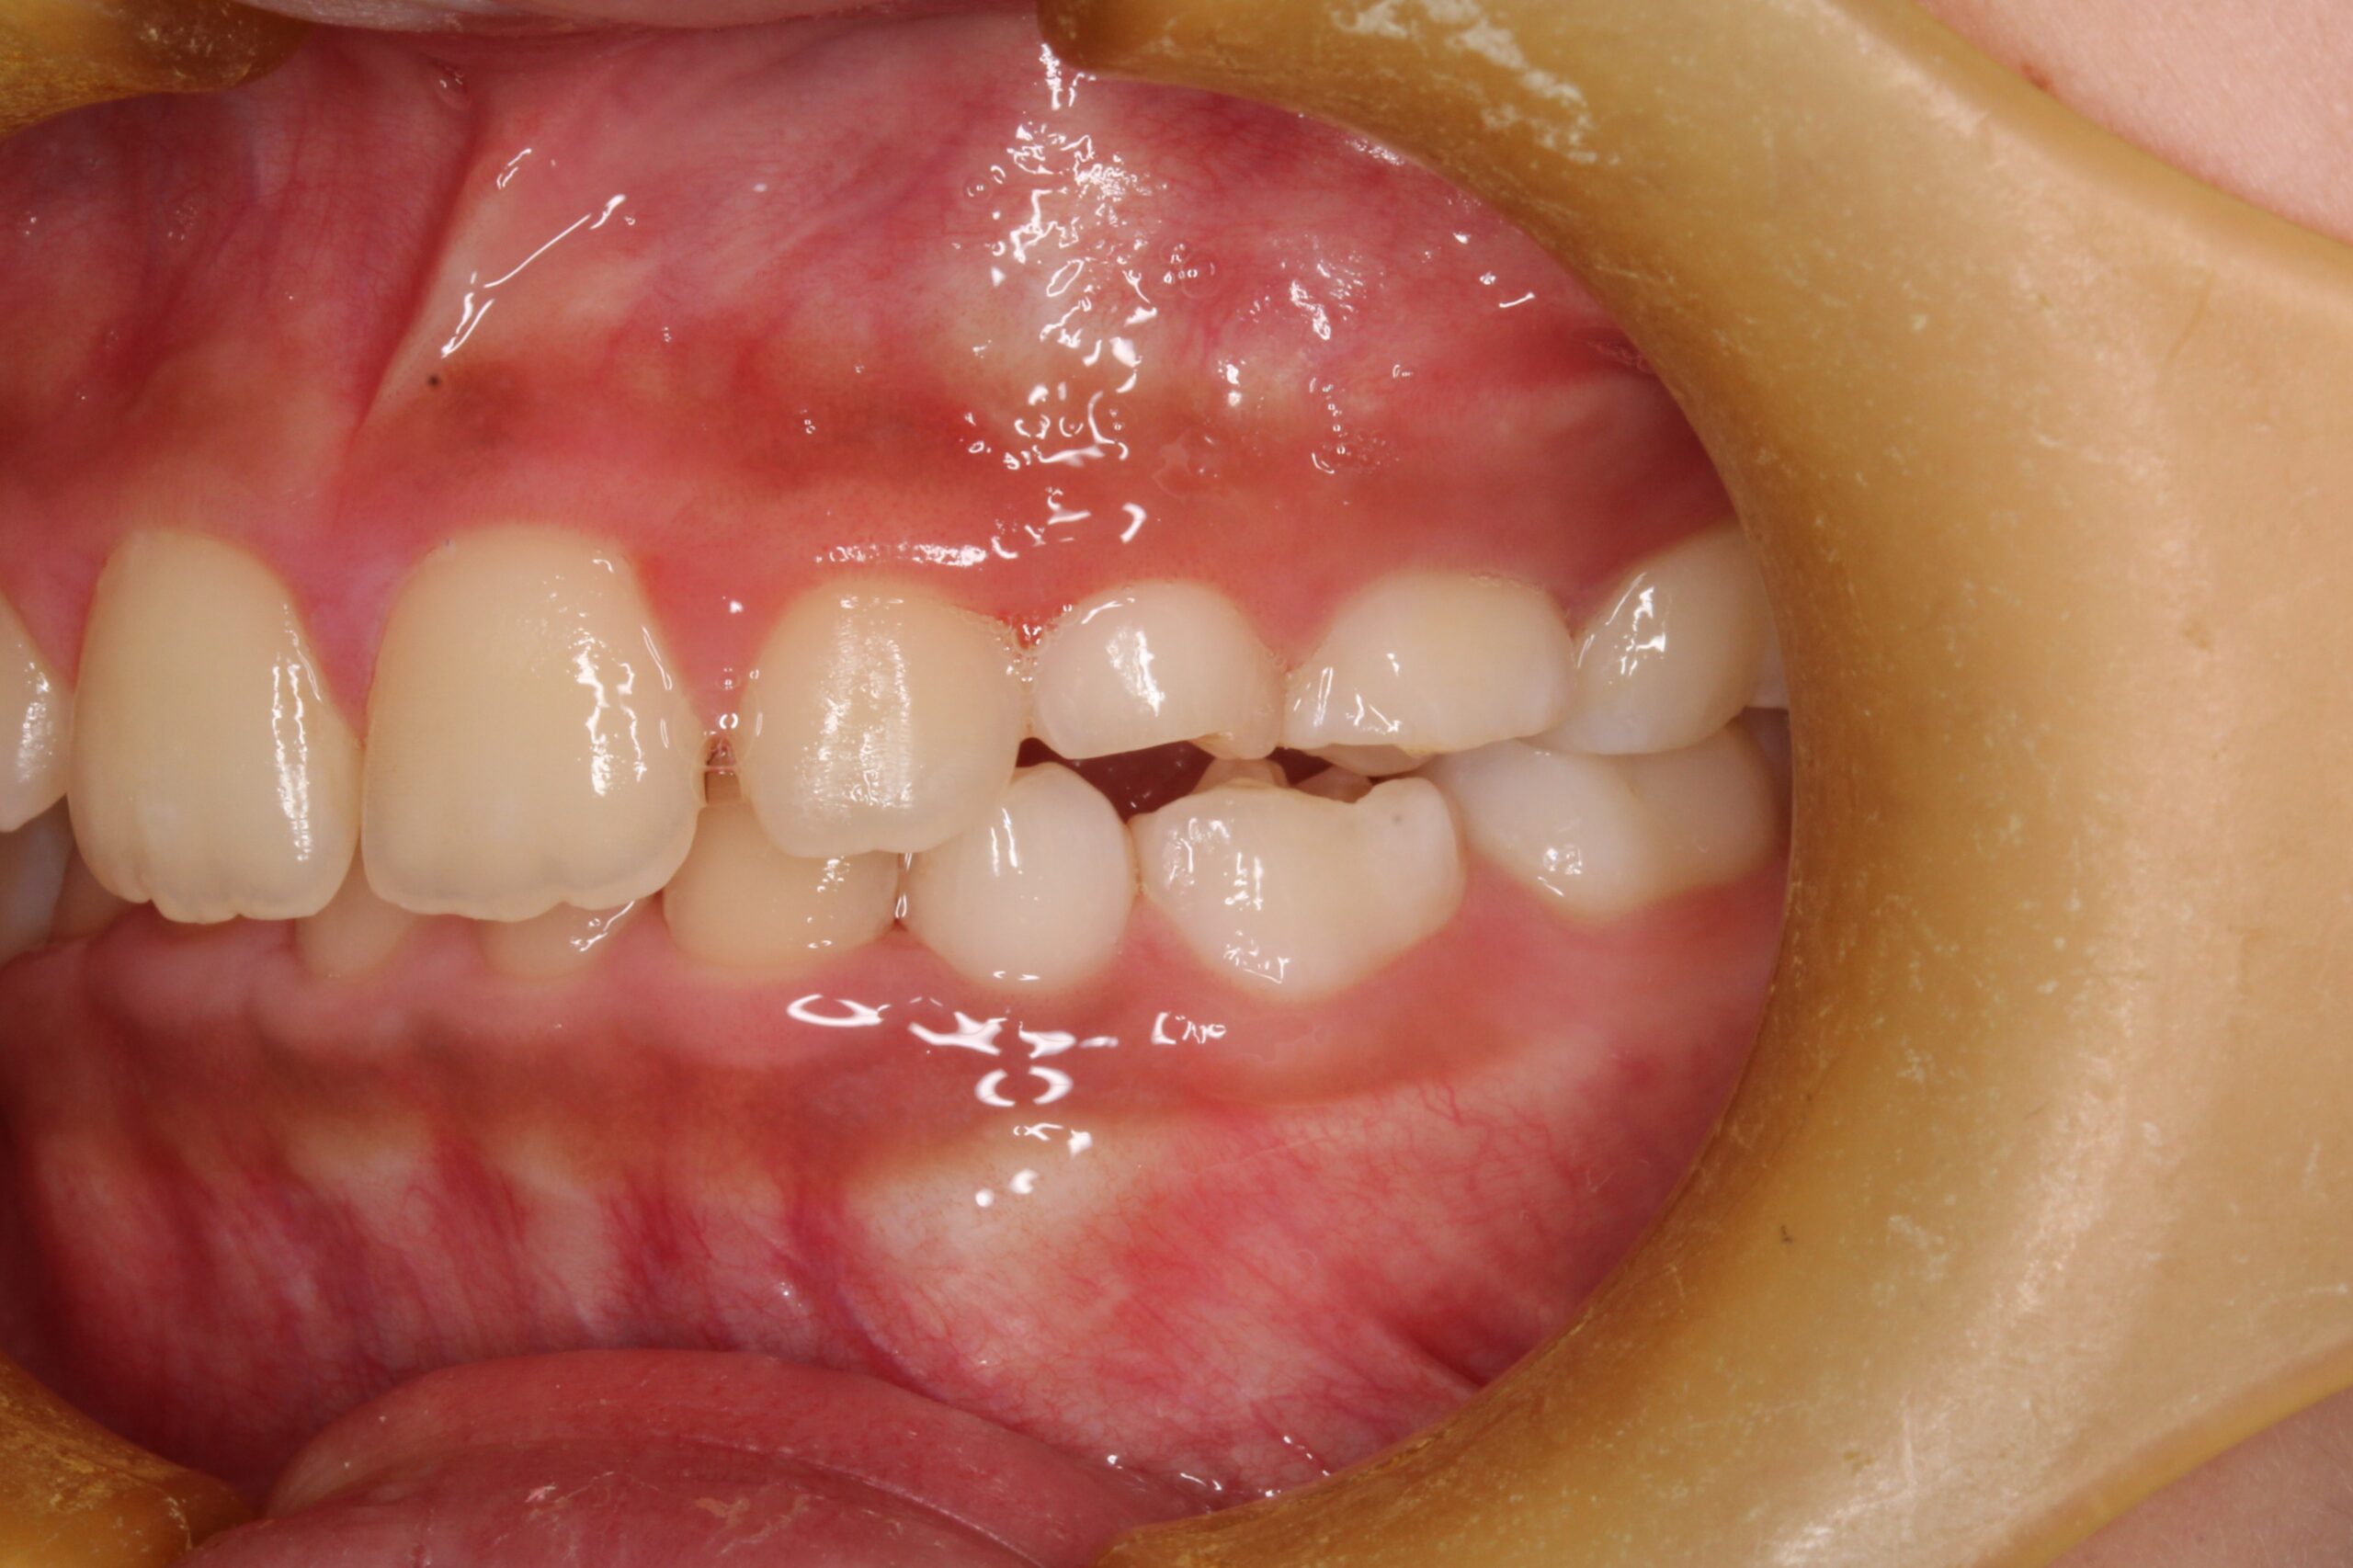

矯正術前:右側

| 主訴 | 下の前歯のがたつきが気になる |

| 治療内容 | 患者様は、下の前歯のがたつきを気にされており、矯正検査後叢生Ⅰ級と診断いたしました |